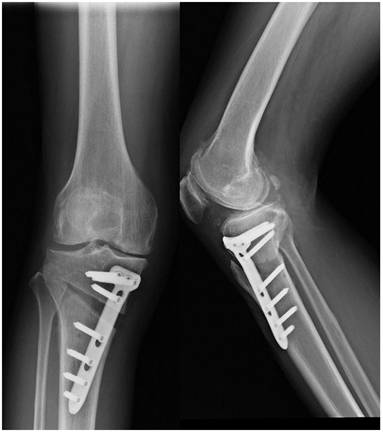

The HTO surgical methods include: closing wedge osteotomy, opening wedge osteotomy, dome osteotomy, and “en chevron” osteotomy. The most commonly applied surgical methods are medial opening wedge osteotomy and lateral closing wedge osteotomy. Firstly, a 5-cm longitudinal incision should be made along the leading edge of the pes in the medial upper tibia. The pes was distally retracted to expose the superficial medial collateral ligament, and the patellar ligament was pried open with a blunt pry plate to reveal the tibial tubercle. Using the fibula head as a reference hinge exit point, two 2.5cm Kirschner needles were inserted into the medial tibia at 3cm from the tibial plateau. The two Kirschner needles must be parallel and pointed at the hinge pivot point identified before surgery. The X-ray fluoroscopy was used to confirm accurate positioning and an optimal osteotomy surface. The osteotomy should be performed along the osteotomy line, with approximately 1 cm of the lateral tibial hinge cortex area being preserved. Slowly open the medial osteotomy gap using the “Stacking osteotomes” method [40]. Fluoroscopy should be used to ensure whether the lower limb mechanical axis has been correctly corrected (the lower limb force line passes through the Fujisawa point). Insert Tomofix steel plate, drill holes in sequence, and secure with screws. Confirming through fluoroscopy that the position of the steel plate screws is well, and suture the wound layer by layer after rinsing (Figure 2).

Figure 2

Postoperative X-ray of the knee joint in both anteroposterior and lateral positions after HTO.

Int J Med Sci Image